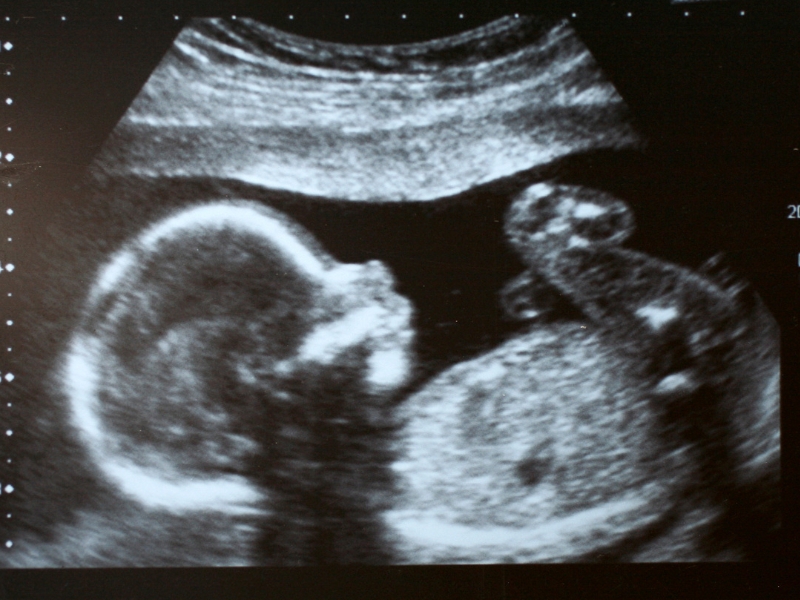

- Các bác sĩ thường sẽ ước tính cân nặng và chiều cao của thai nhi bằng các máy siêu âm, tuy nhiên cần lưu ý rằng đây chỉ là các con số trung bình; mỗi em bé sẽ có tốc độ phát triển của riêng mình.

Các bác sĩ thường sẽ theo dõi sự phát triển và tăng trưởng của em bé bằng cách siêu âm, đồng thời quan sát về chiều cao tử cung. Nếu có bất kỳ lo ngại nào hoặc bạn có thai kỳ có nguy cơ cao, chắc chắn rằng bạn sẽ phải siêu âm nhiều lần hơn để kiểm tra kích thước của em bé.

Khi siêu âm, các bác sĩ có thể sẽ thực hiện nhiều cách tính toán khác nhau, ví dụ như đo chu vi, đường kính đầu, chu vi bụng và chiều dài xương đùi… để có thể ước lượng được kích thước của em bé.